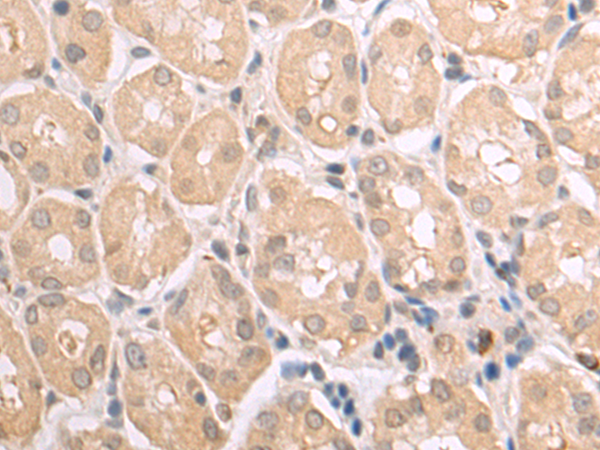

分类: 科研抗体货号: P07473别名: EBN; BFNC; EBN1; NACHR; NACRA4; NACHRA4应用: WB,IHC反应种属: Human

分类: 科研抗体货号: P07452别名: ME; HME; MME; MMP-12应用: WB,IHC反应种属: Human

分类: 科研抗体货号: P07433别名: NRAGE, DLXIN-1应用: WB,IHC反应种属: Human, Mouse, Rat

分类: 科研抗体货号: P07472别名: LC17; ESMLC; LC17A; LC17B; MLC-3; MLC1SM; MLC3NM; MLC3SM; LC17-GI; LC17-NM应用: WB,IHC反应种属: Human, Mouse, Rat

分类: 科研抗体货号: P07451别名: KMLC; MLCK; MLCK2; skMLCK应用: IHC反应种属: Human, Mouse, Rat

分类: 科研抗体货号: P07432别名: GMA; S-MAG; SIGLEC4A; SIGLEC-4A应用: WB,IHC反应种属: Human, Mouse, Rat

分类: 科研抗体货号: P07471别名: MYHa; MYHSA1; MyHC-2x; MyHC-2X/D应用: IHC反应种属: Human, Mouse

分类: 科研抗体货号: P07450别名: MIC-A; PERB11.1应用: WB,IHC反应种属: Human

分类: 科研抗体货号: P07464别名:应用: IHC反应种属: Human

分类: 科研抗体货号: P07470别名: CMH1; MPD1; SPMD; SPMM; CMD1S; MYHCB应用: IHC反应种属: Human, Mouse, Rat